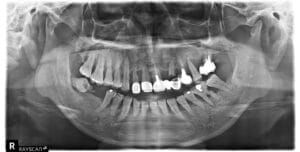

上顎缺牙導致進食不變,想尋求重建方式 因上顎後牙缺牙時間過久造成大量骨質萎縮,需先做鼻竇增高及補骨手